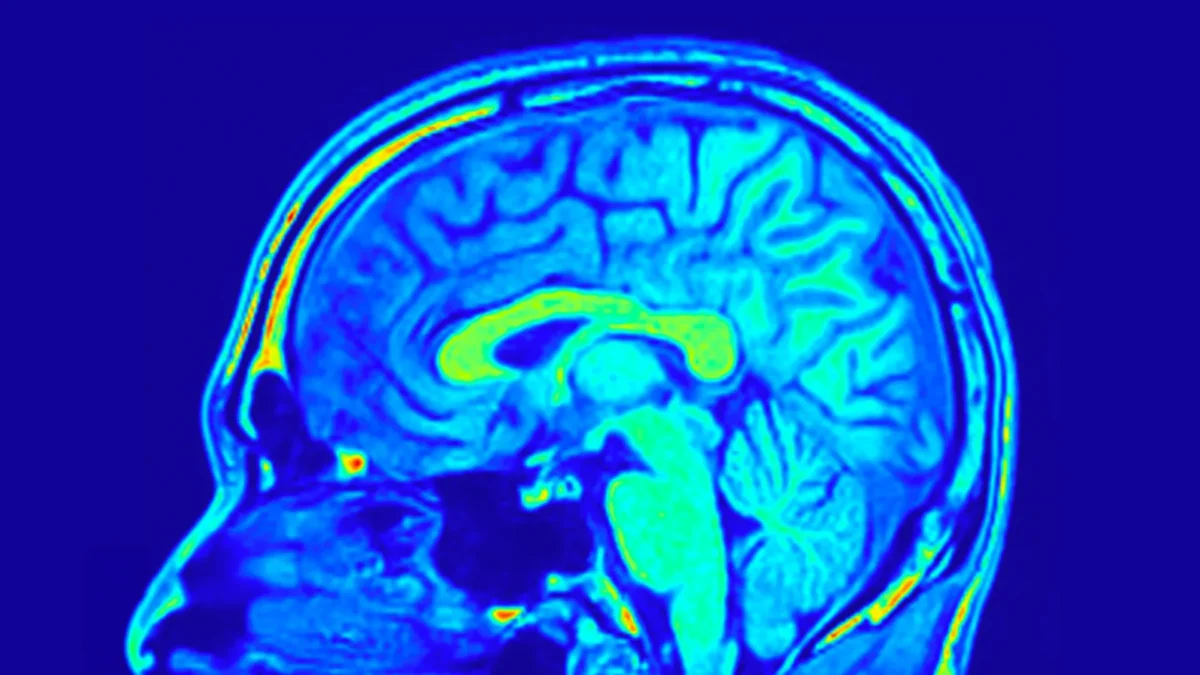

Para acompanhar os resultados, a equipe mediou a gravidade da depressão utilizando a Escala Hamilton de Depressão de 24 itens (HAMD-24), um questionário clínico amplamente utilizado. Eles também coletaram amostras de sangue periférico e realizaram ressonâncias magnéticas (RM) para examinar as mudanças na estrutura e na biologia cerebral.

Os dados de imagem cerebral revelaram insights ainda mais profundos. Os pesquisadores descobriram que redes específicas formadas por estruturas cerebrais podiam prever mudanças nos escores de depressão em ambos os grupos de tratamento. Essas redes refletem como diferentes regiões do cérebro estão organizadas e conectadas.

Mais surpreendentemente, certos padrões cerebrais eram preditivos apenas em pacientes que tomavam a Pílula Yueju. Esses padrões foram baseados na profundidade dos sulcos e na espessura cortical, que descrevem a dobra da superfície cerebral e a espessura da camada externa do cérebro. Ambas as características estão ligadas ao desenvolvimento e à função cerebral. Análises adicionais mostraram que a rede visual do cérebro desempenhava um papel particularmente importante na previsão de melhorias tanto nos sintomas de depressão quanto nos níveis de BDNF entre aqueles tratados com a Pílula Yueju.

Considerando todos os achados, as evidências sugerem que padrões de redes cerebrais identificados por meio de ressonâncias magnéticas poderiam ajudar a prever como pacientes individuais com TDM responderiam ao tratamento com a Pílula Yueju. Essa abordagem vai além da tomada de decisões baseada em sintomas e aponta para uma terapia antidepressiva mais personalizada.